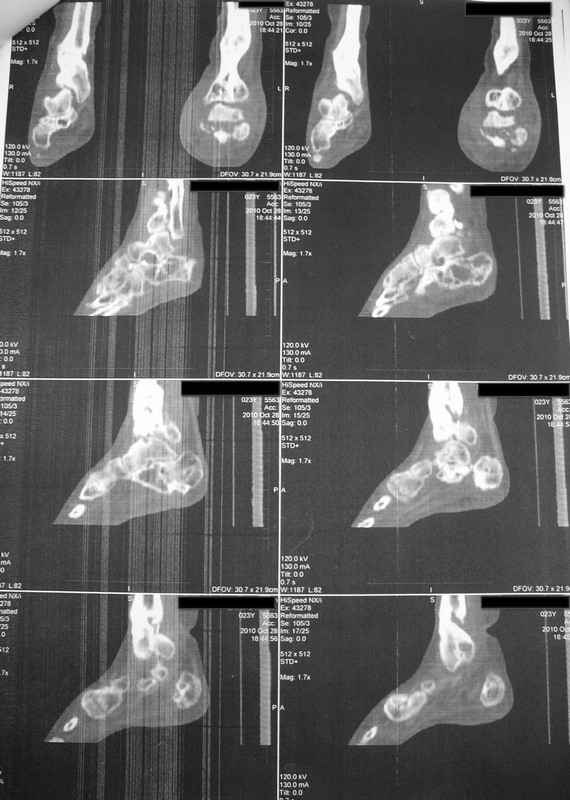

Молодая девушка со сросшимися многооскольчатыми переломами пяток и голеней.Young girl with fractures of the calcaneus Больная Н., 25 лет, падение с высоты (2008 г.). Жалобы на боли в области голеностопных суставах, в области пяток при ходьбе. Лечилась в аппаратах внешней фиксации по поводу открытых оскольчатых переломов обеих голеней, переломов пяток. Далее по поводу несросшихся переломов голеней –ЧКОС аппаратами внешней фиксации. Переломы срослись, аппараты демонтированы весной 2010г. В левой пяточной области в месте проведения спицы имеется сукровичное отделяемое. При ревизии гноя нет. Чем помочь девушке?

Patient N., age 25, falls from heights (2008). Complaints of pain in the ankles, in the heel when walking. She was treated by external fixation on open comminuted fractures of both legs, fractures of the calcaneus. Then she was treated by external fixation from nonunion of both legs. Now fractures are fused, apparatuses removed in the spring of 2010. How to help a girl?